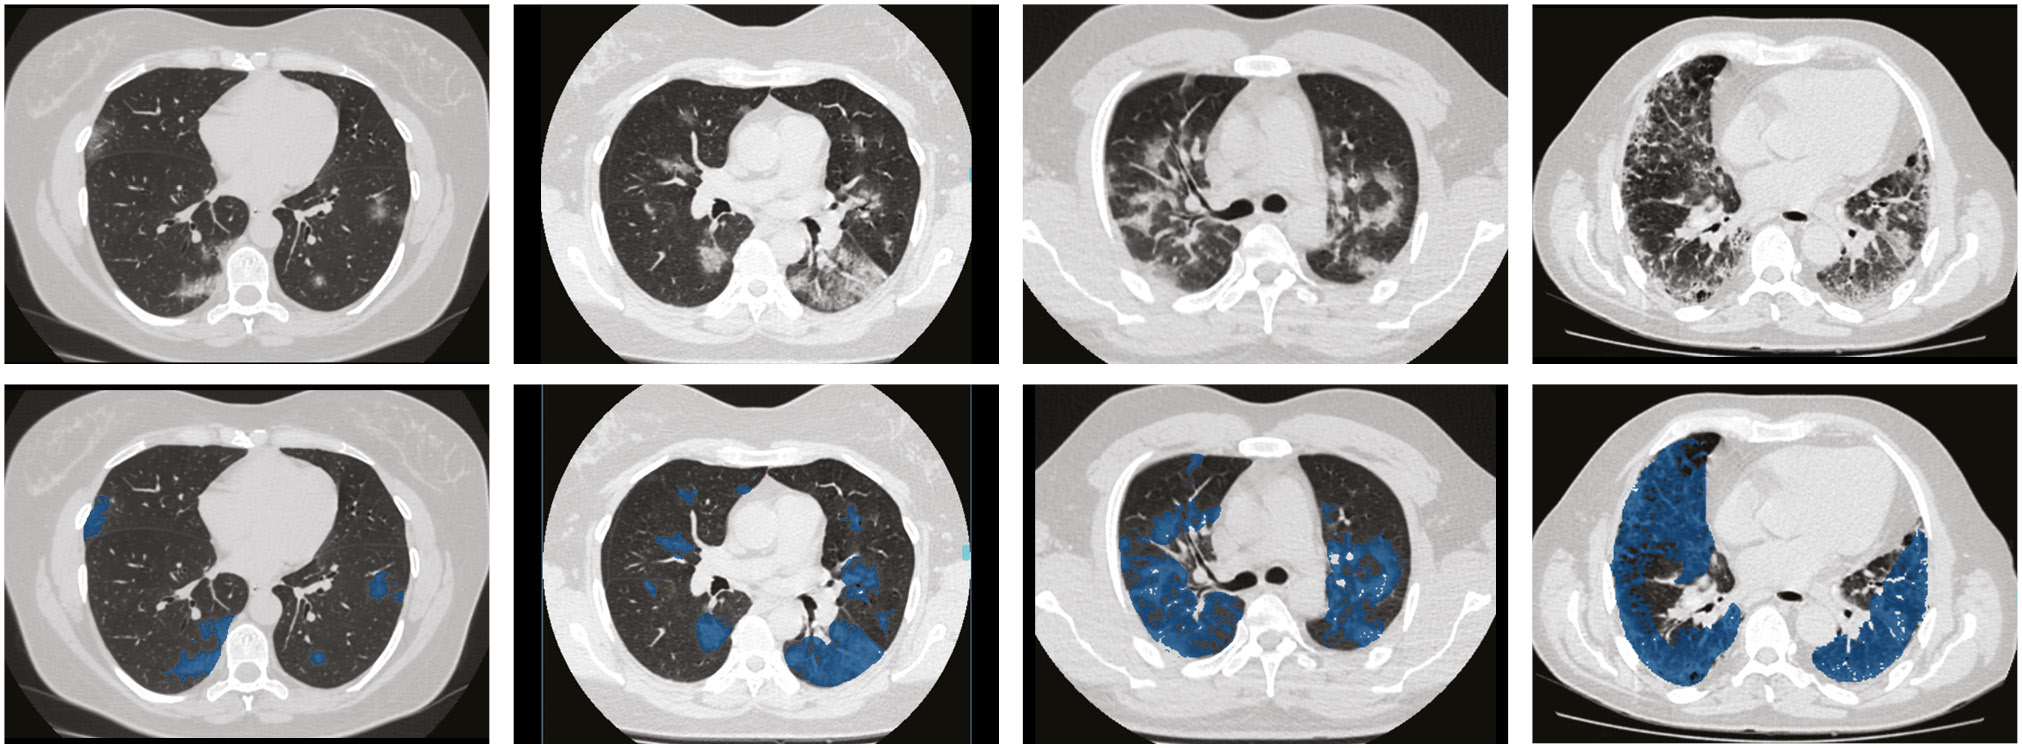

Figure 2: Examples of chest CT scans of patients with varying degrees of COVID-19 severity. Left to right, upper row: axial CT slices of patients with COVID-19 from mild (CT-1) to critical (CT-4) severity. Left to right, lower row: same CT data after tagging.

At the first stage, all the examinations (n=1110) were distributed into five categories according to the classification (Table 2). The number of cases by categories: CT-0, 254 (22.8%); CT-1, 684 (61.6%); CT-2, 125 (11.3%); CT-3, 45 (4.1%); and CT-4, 2 (0.2%). Second, each study was saved in the NIfTI format and archived in the Gzip archive. During this process, only every 10th image (Instance) was saved in the final study file.

A small number of the CT scans (n = 50) was tagged by specialists from the Research and Practical Clinical Center for Diagnostics and Telemedicine Technologies of the Moscow Department of Health. During the markup, positive (white) pixels on the corresponding binary pixel mask were selected for each of the images. The obtained masks were saved in NIfTI format and then converted to the Gzip archives. MedSeg® annotation software (© 2020 Artificial Intelligence AS) was used to create the binary masks.

This software was used to tag only COVID-19 lesions, including ground-glass opacities, consolidation, small vessels, and bronchioles. The density thresholds for tagging were from −700 HU to −130 HU, but it could differ depending on the breathing depth. We excluded large vessels and bronchi, visually unchanged pulmonary parenchyma, motion artifacts (respiratory due to cough and respiratory failure), gravitational changes (if it was possible to reliably differentiate them), calcifications, and pleural effusion.